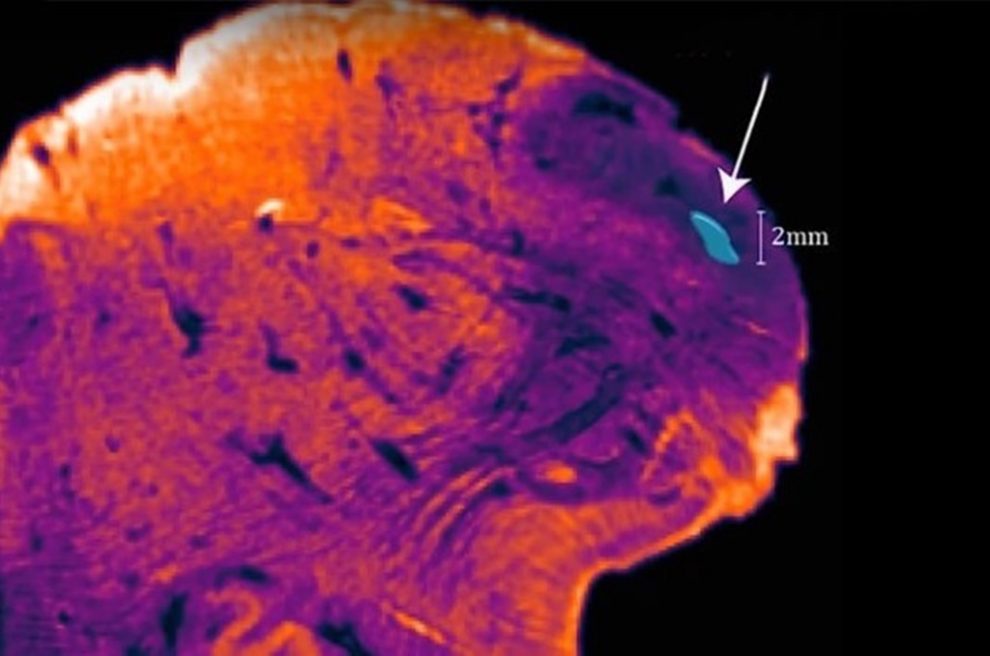

Neurocercetatorul George Paxinos si echipa sa din cadrul centrului australian de Neurostiinte si Cercetare au descoperit nucleul endorestiform, localizat in interiorul (endo) corpului restiform, ce se afla la baza creierului, potrivit Science Alert.

Zona e responsabila de procesarea informatiilor senzoriale si motorii si e implicata in determinarea posturii, echilibrului si miscarii.

“Corpul restiform e precum un rau ce poarta informatia din maduva spinarii catre cerebel,” a declarat Paxinos. “Nucleul endorestiform e o grupare de neuroni si e precum o insula in acest rau.”

Paxinos a descoperit structura inedita cu ajutorul unei proceduri noi, ce permite realizarea unor imagini mai clare ale tesutului creierului. Procedura permite diferentierea celulelor pe baza functiilor lor si nu doar prin intermediul formei, ca alte metode.

Cercetatorii cred ca aceasta structura e responsabila de procesarea si dezvoltarea abilitatilor motorii fine, dat fiind faptul ca lipseste din creierul altor primate.